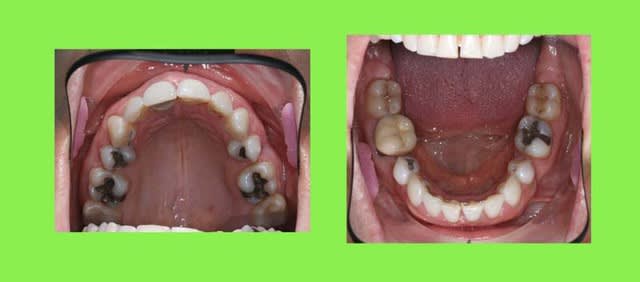

voici un cas qui parait plus qu’acceptable

3 ans de ttt. ODF.

la patiente vient consulter pour refaire ses contentions car elle sent que ses dents bougent (11/12)

elle a été traitée par extraction des 4 P.M. !!!

2 maxillaires 1 uhmamu - Eugenol

elle a cassé la contention collée du haut, remplacée par une plaque à bandeau

et la contention du bas laisse apparaître un diastème

je lui ai répondu qu’il fallait reprendre le ttt.

elle ne veut pas

je ne peux pas grand-chose pour elle, toutes mes contentions casseront

et ce sera ma faute !